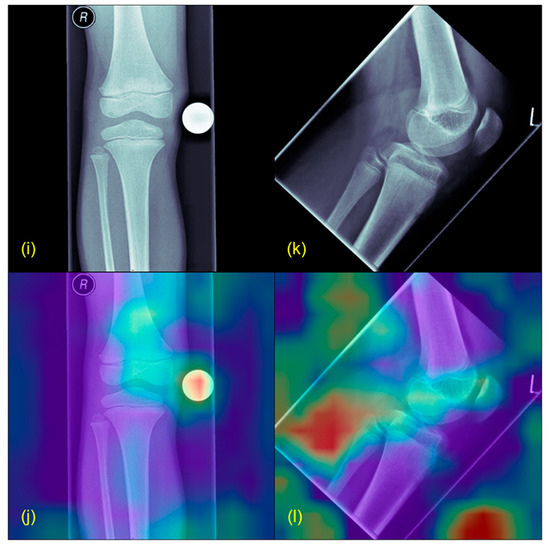

- Selvaraju, R.R.; Cogswell, M.; Das, A.; Vedantam, R.; Parikh, D.; Batra, D. Grad-CAM: Visual Explanations from Deep Networks via Gradient-Based Localization. Int. J. Comput. Vis. 2020, 128, 336–359. [Google Scholar] [CrossRef]